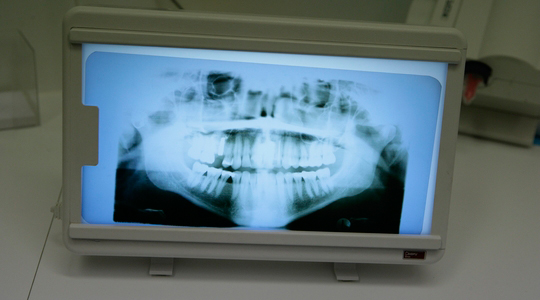

Röntgen

Die Zähne zu röntgen ist ein wichtiger Teil der Diagnose.